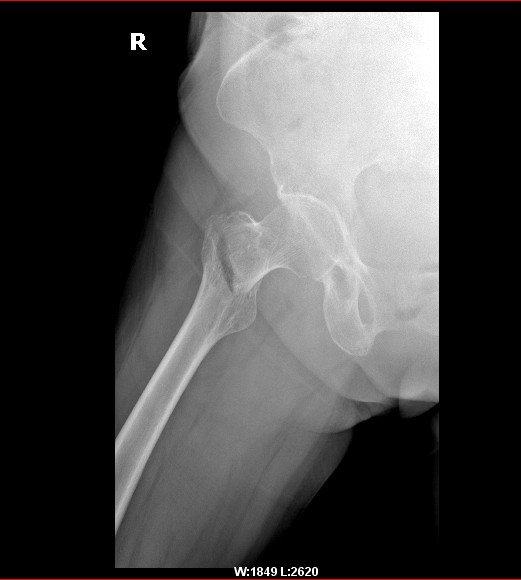

以下是引用zxl51642在2010-3-30 19:22:00的发言:[br]粗隆间骨折,移位不明显,打三翼钉固定即可,血供没有影响不用换头,髋关节(-)

以下是引用拾荒者在2010-3-30 20:20:00的发言:[br]右侧股骨粗隆间骨折,右侧髋关节间隙变窄,建议ct扫描看髋臼有否骨折。